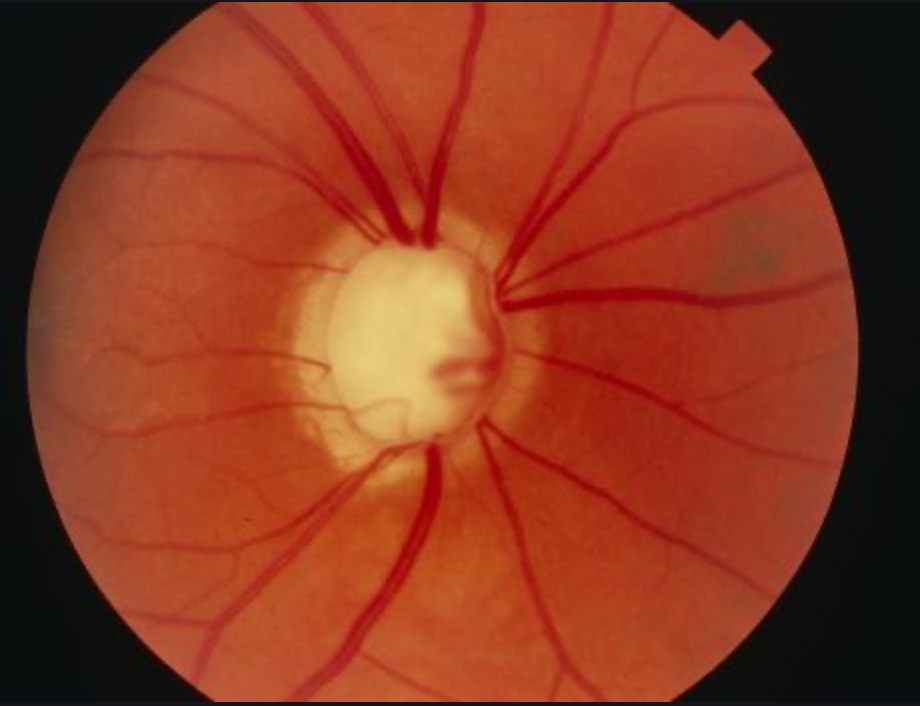

Glaucoma

Open Angle Glaucoma